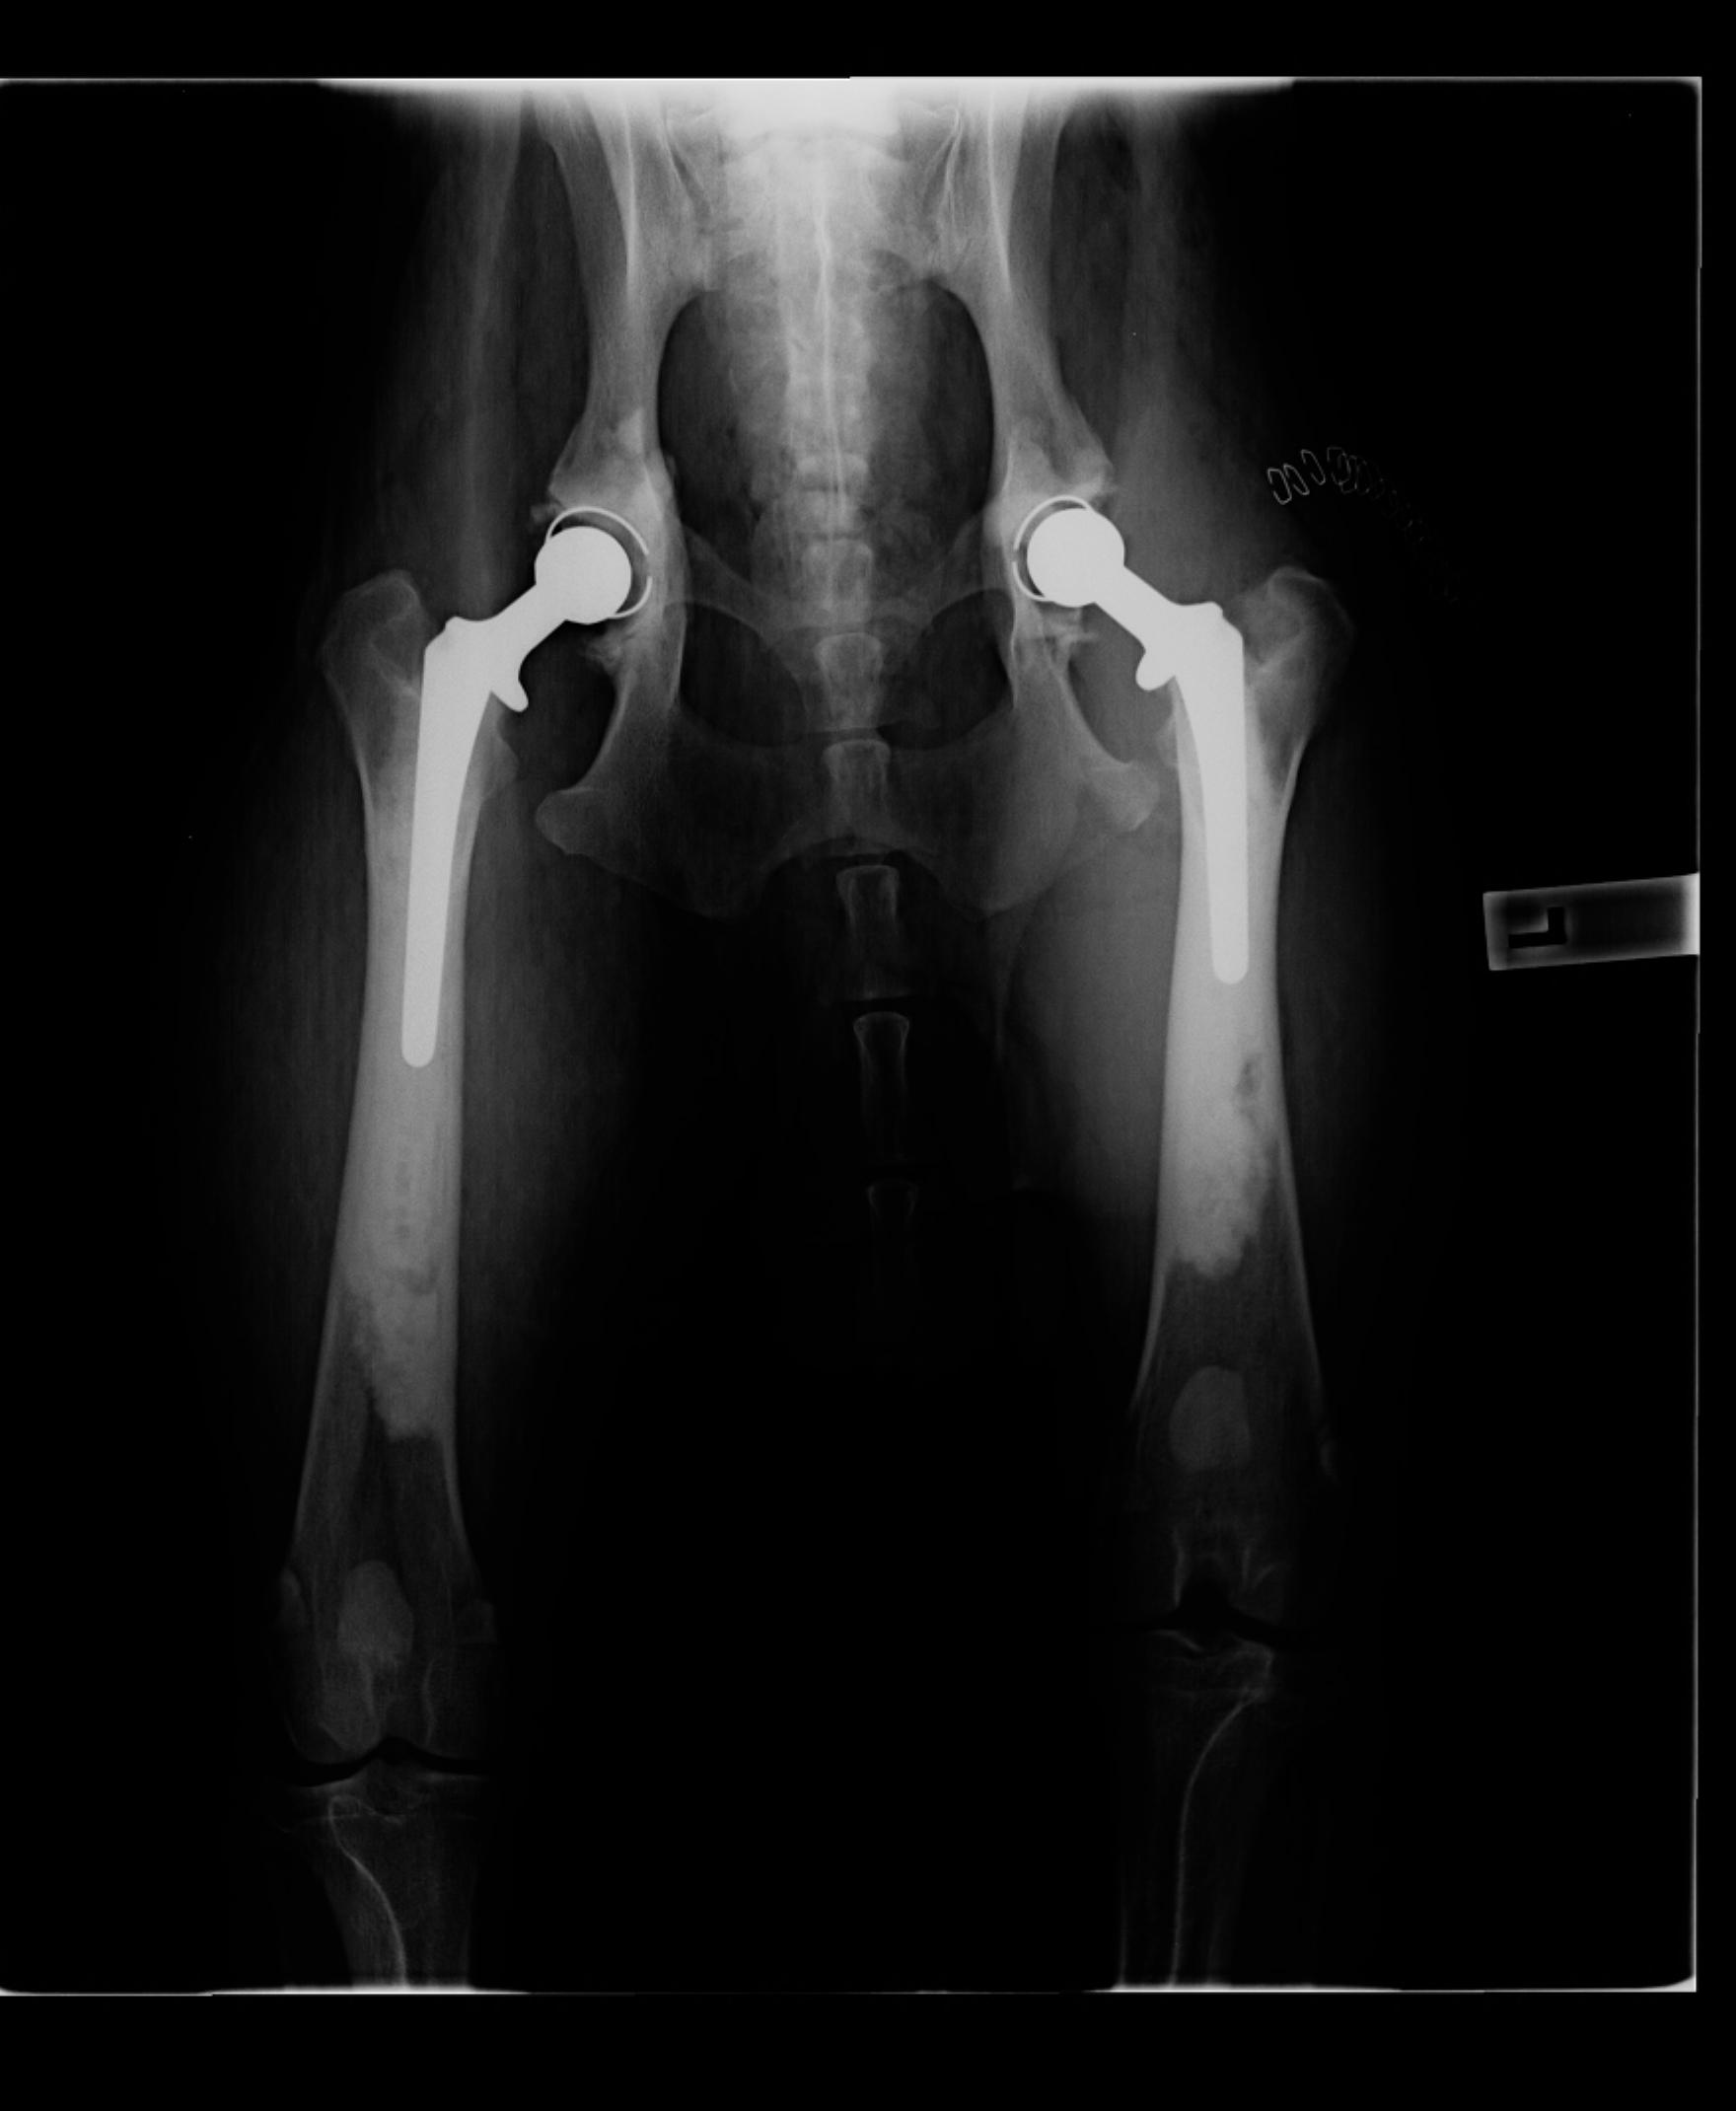

bianca.a Posted August 5, 2014 Share Posted August 5, 2014 Hi and I am so very sorry for you both. Yes a hip replacement can be done. My male GSD had his first total hip replacement at 14 months (I think) and then months ago had his other side done. You would never know (apart from my bank balance!). I wish you the very best. Here his Cooper now (aged 2) Link to comment Share on other sites More sharing options...

bianca.a Posted August 5, 2014 Share Posted August 5, 2014 Also the specialists who I consulted with (multiple including the one who did the surgeries) said that the ball, socket and stem will last the lifetime of the dog so that is a huge positive. Cooper suffered with his first op but that was due to his scrotum being burnt by clippers. He was more bothered by that then the hip. This time round was much easier. You just have to keep them contained and quiet for the first 6 weeks which is hard. Link to comment Share on other sites More sharing options...